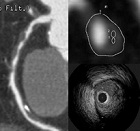

Coronary Computed Tomography Angiography:

Using multi-detector computed tomography (MDCT), a whole heart can be scanned during a few seconds breath-hold on an outpatient basis. MDCT-coronary angiography can detect stenoses and plaques. The information is useful to decide on treatment strategies. We also evaluate the mechanism of coronary atherosclerosis, which will be useful to predict and prevent the development of acute coronary syndrome.